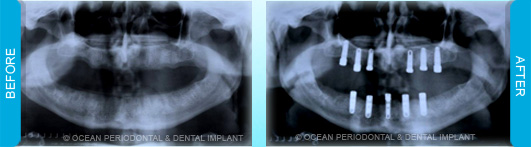

Dental implants are commonly used to replace missing or lost teeth in order to ensure patient comfort, function, and aesthetics. Indeed, there are many treatment options for management of missing teeth, such as bridges, and partial/complete dentures.

Nonetheless, numerous studies have demonstrated that implant-supported restorations are generally deemed to have superior functional and aesthetic outcomes. Furthermore, there are cases where dental implants may be the only logical choice for the restoration of function and aesthetics.

Dental implants can be used to replace missing teeth. There are many benefits to this type of treatment.